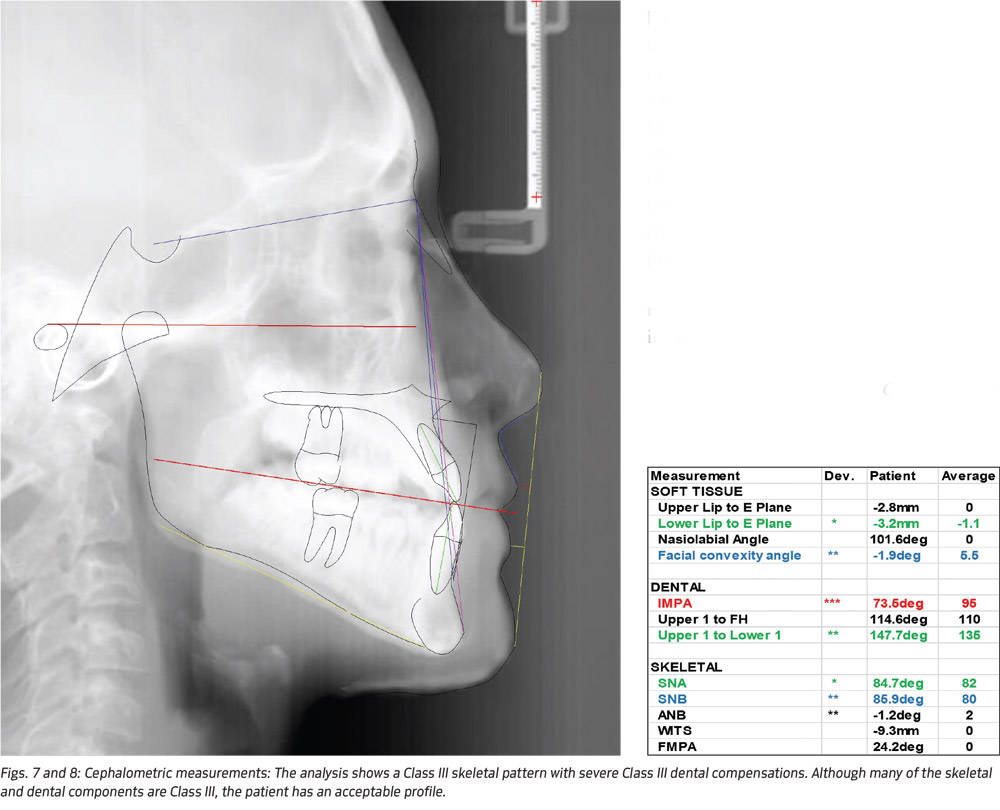

A 13-year-old male presented for treatment with slight overbite and overjet, and maxillary canines actively erupting toward the buccal (Fig. 5). The posterior occlusion was Class I molar left and full step Class III molar on the right side (Fig. 6), resulting in a significant mandibular midline discrepancy. The patient had a straight facial profile, good lip competency and mild chin deviation to the left. In spite of the asymmetric Class III dentition, the resulting chin deviation was mild enough to be considered within normal limits (Figs. 7-8).

Cephalometric analysis revealed a strong Class III component with severe dental compensation. At 73 degrees, the lower incisors were retroclined approximately 20 degrees from the norm. Although ANB was only slightly negative, the Wits appraisal came out to -9.3mm. Because of the severity of the Class III skeletal component and the patient being in active growth, the likelihood of future surgery was discussed before any treatment.